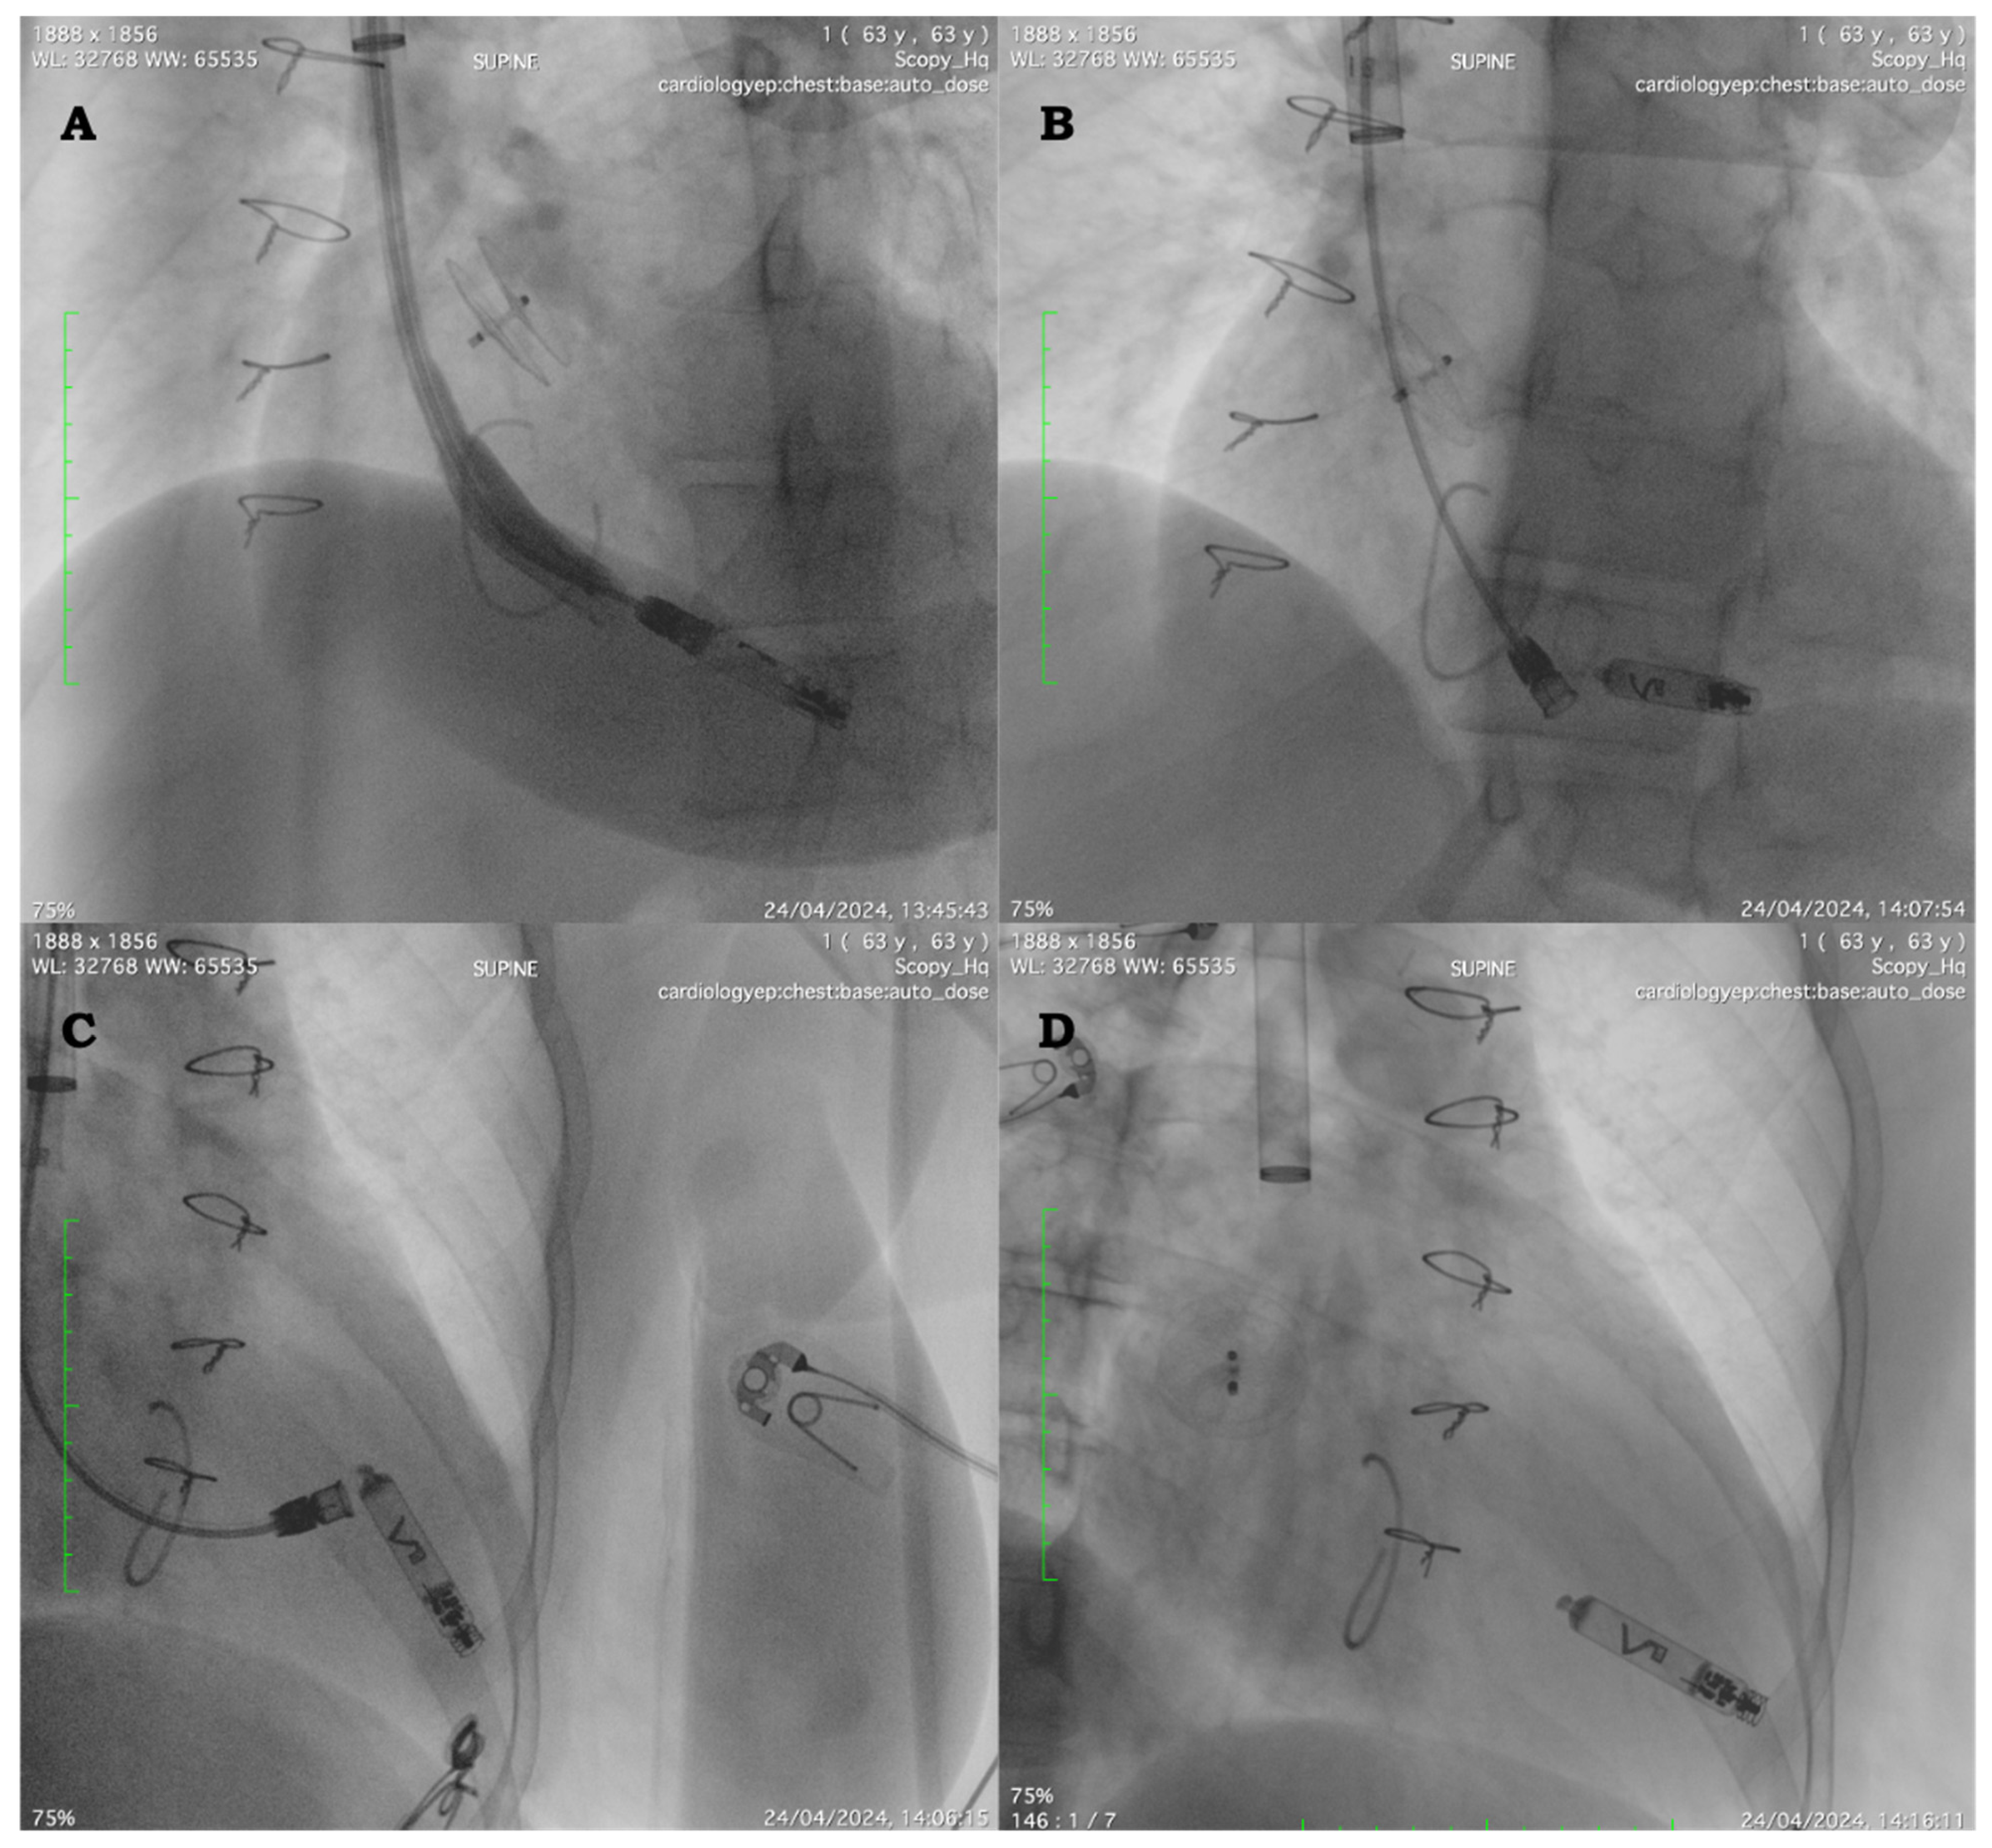

The procedure was performed in the fasting state and under moderate conscious sedation with intravenous boli of midazolam hydrochloride (0.03–0.05 mg/kg) and fentanyl citrate boli (0.7–1.4 mcg/kg) for short-term analgesia plus continuous infusion of dexmedetomidine. After the patient was prepped in a sterile fashion, mepivacaine 1% was used to infiltrate the skin between the two heads of the sternocleidomastoid muscle. Ultrasound-guided right jugular venous access was obtained utilizing the Seldinger technique, and a super-stiff Amplatz wire (Boston Scientific, Malborough, MA, USA) (180 cm, 0.035 cm) was passed through the 8 Fr sheath and advanced down to the inferior vena cava. Consecutive up-sizing via a 4 Fr size increase to a 24 Fr dilator was performed. Finally, the 27 Fr (outer diameter) Abbott Aveir sheath was passed over the wire into the mid-right atrium. Subsequently, the Aveir, on a deployment catheter (23 Fr), was passed through the 27 Fr outer sheath and moved across the TV at first into an apical RV septal position under fluoroscopic and echocardiographic guidance. Despite the good fluoroscopic position on angiograms and satisfactory R-wave sensing (7.6 mV), pacing impedance and thresholds were suboptimal on contact mapping before active fixation (3.5 V @ 0.4 ms). A second attempt was made at a higher position, and the device was deployed after a good contact mapping test with the current proprietary program surface analyzer using conductive telemetry with skin electrodes connected to the patient’s torso. The final threshold was stable at 1.25 V @ 0.4 ms, with stable impedance and good RV sensing (6.4 mV). The stability test and final position are shown in Figure 1A–D. At the end, a figure-of-eight suture was placed to remove the introducer.

Figure 1. (A) Left anterior oblique (LAO) 30 degree. Position of the leadless device on the septum. The tricuspid valve annulus and the atrial septal closure device are evident. (B) LAO 30 degree. Stability testing after leadless device implantation. (C) Right anterior oblique (RAO) 30 degree. Stability testing after leadless device implantation. (D) RAO 30 degree. Final position after delivery system release.